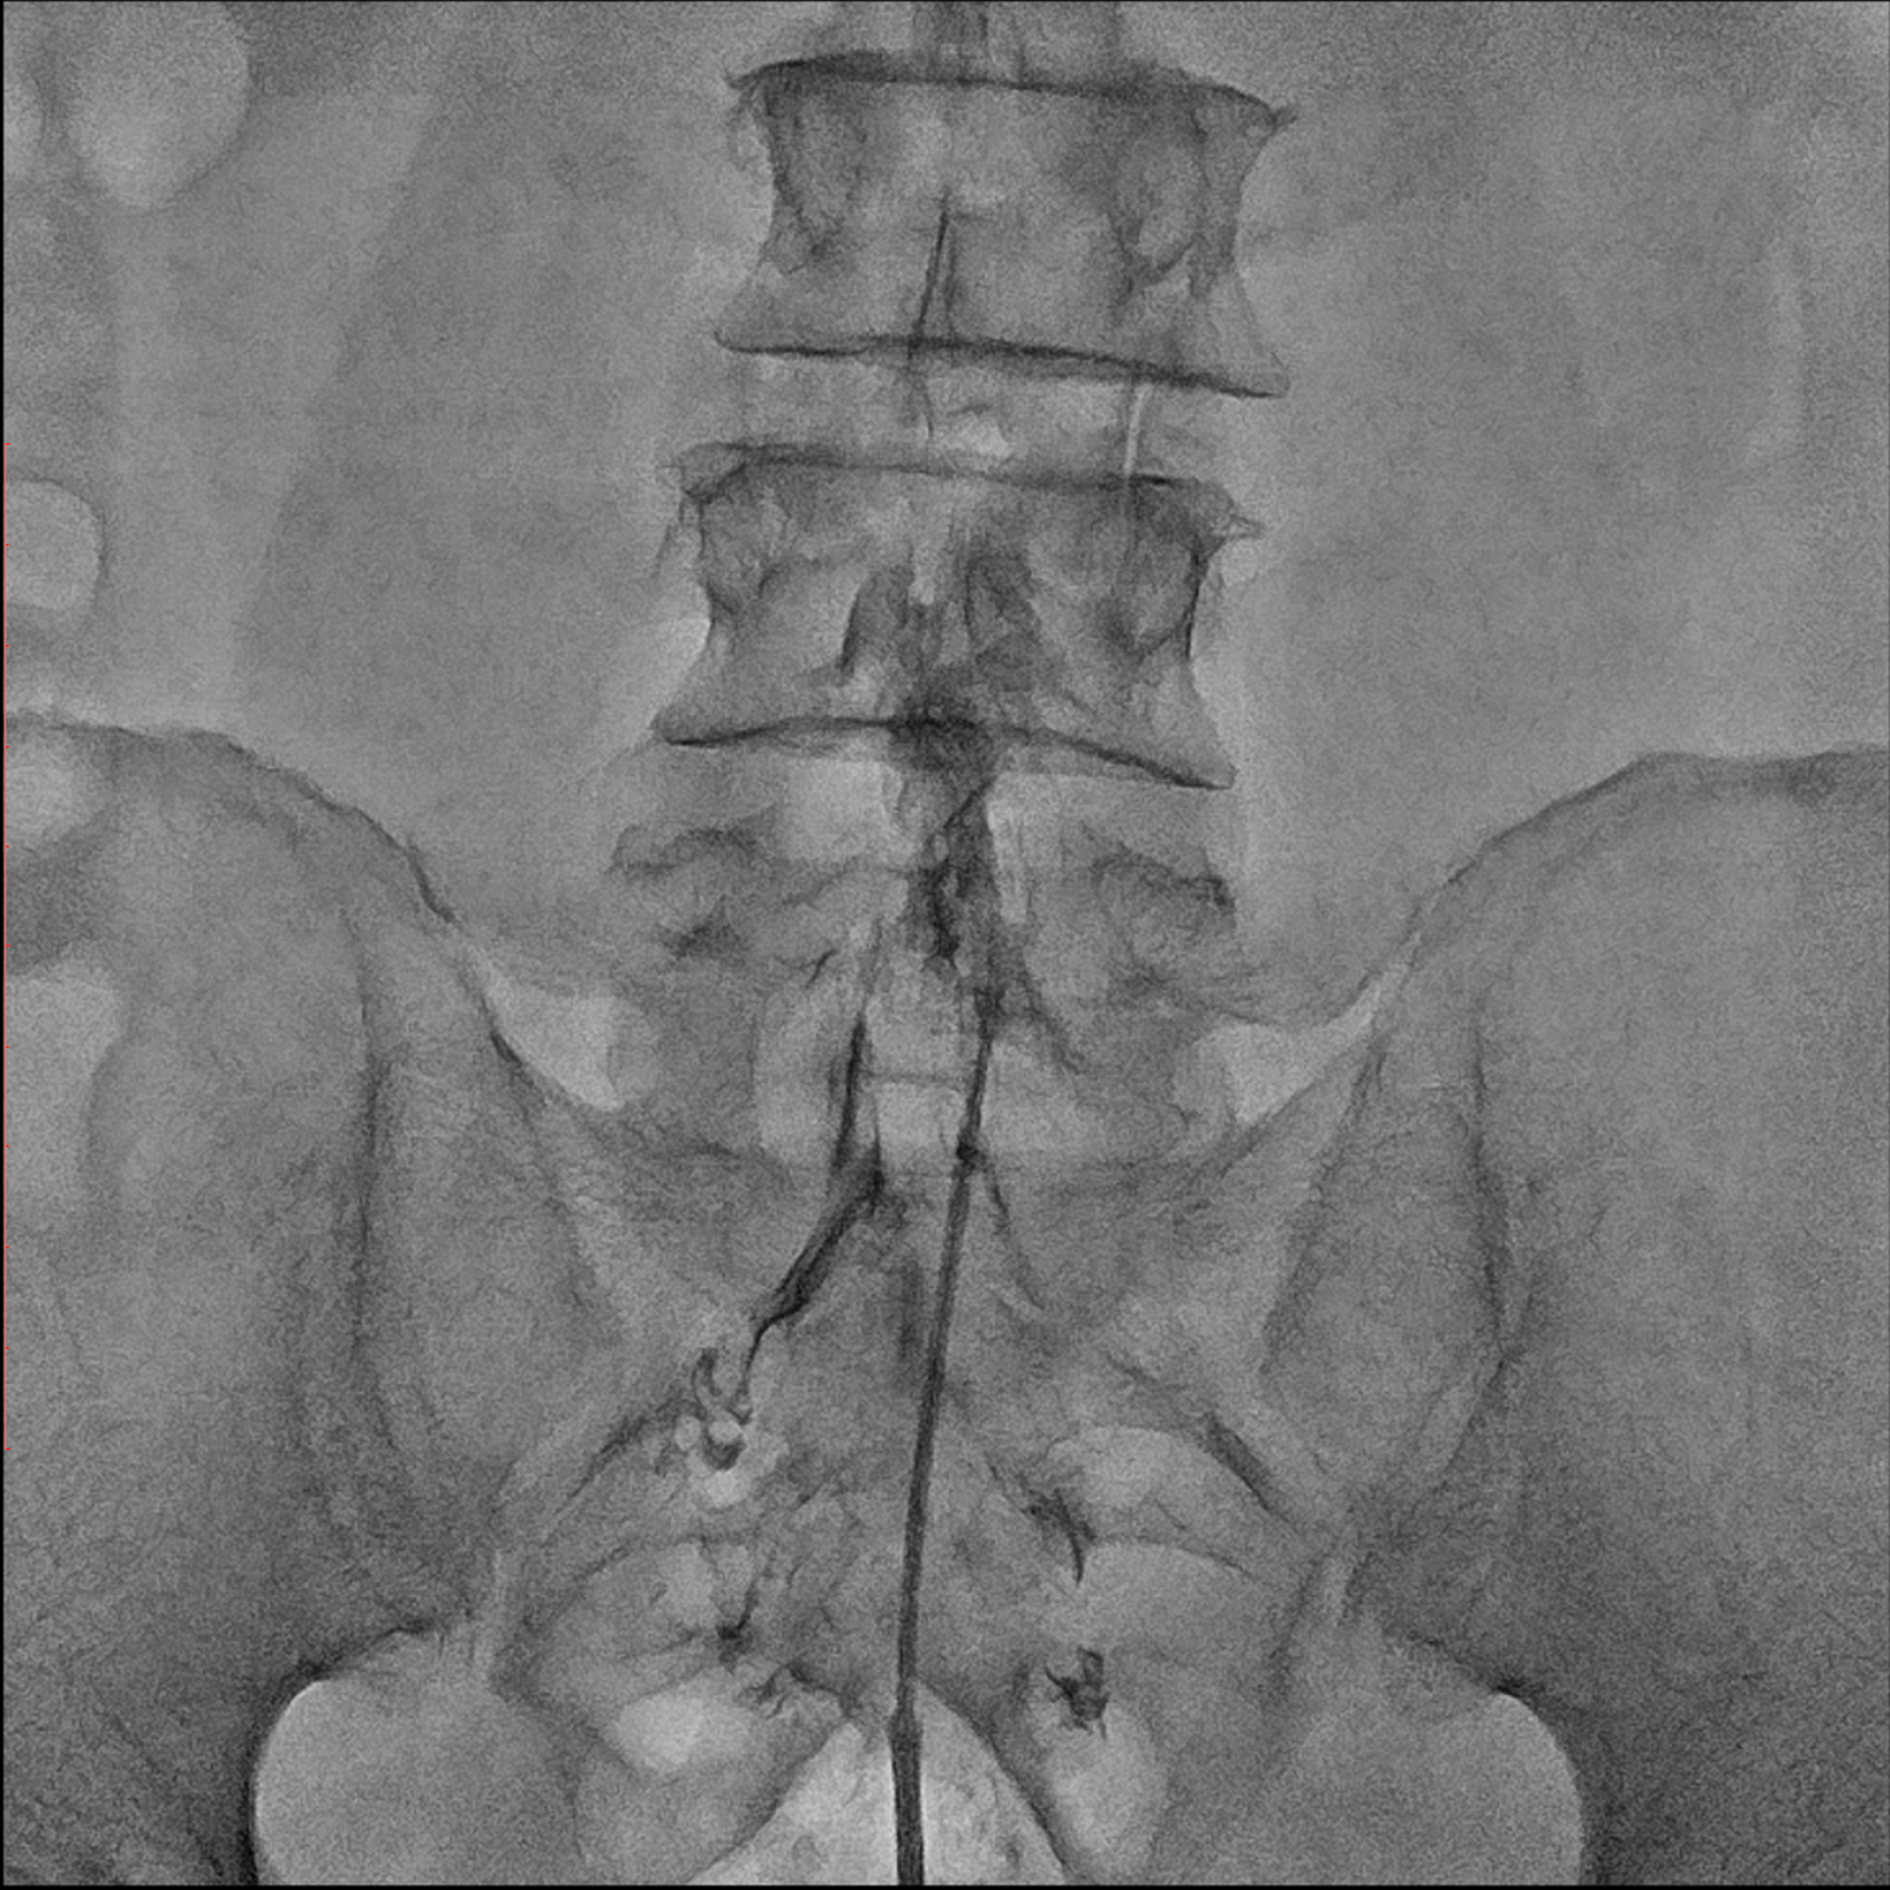

경막외 유착박리술, Epidural Neuroplasty